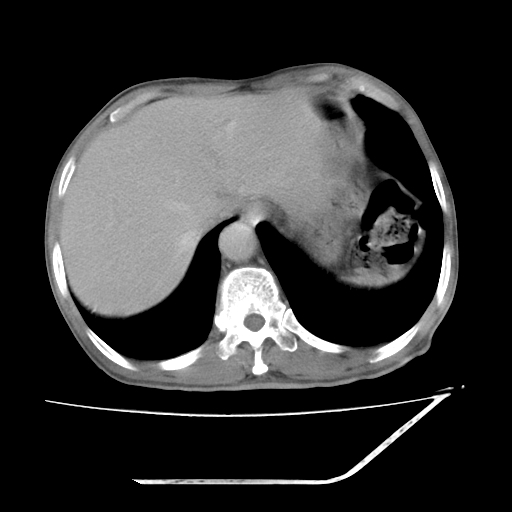

增强

支持右侧肾盂癌伴肾静脉瘤栓形成可能性大,右肾结石.肝右叶后段低密度影,不除外转移.

右肾盂旁ca并肾静脉瘤栓形成/肾功能降低。

右肾结石。

支持 右侧肾盂癌伴肾静脉瘤栓形成可能性大,右肾结石;肝右叶后段低密度影,不除外转移。

1.右侧肾盂癌伴肾盂积水。

2.肾脏功能减退,原因有:(1)肾动脉受侵。(2)肾静脉受侵(3)肾积水,等。本例,肾动脉显影较好,但受压明显;肾静脉无明显显示,受压或静脉癌栓,下腔静脉腔内未见明显充盈缺损。